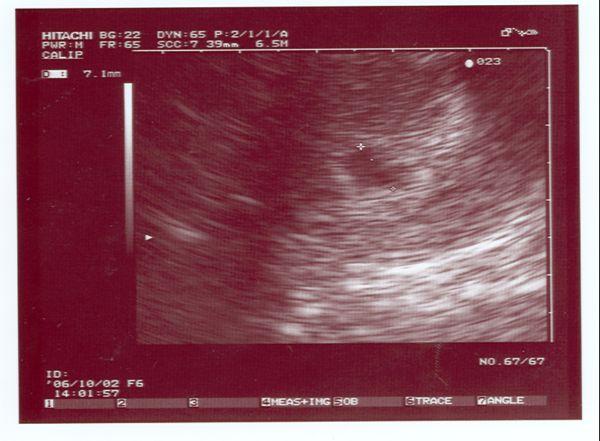

Megjöttünk a dokitól és ime a kép!

Remélem jól sikerült a képet felraknom!!!

Hála az égnek minden rendben!Az adatok a következők:

CRL:51 mm

Nyakiredő:1 mm

Fej mérete:20 mm

Jó szívmüködése van a picinek,egészségesek vagyunk!Szépen növekedik a pocaklakó!!